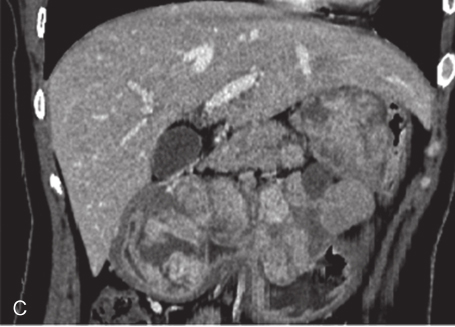

全腹部增强CT:① 胃体-胃小弯侧壁-胃窦及肝胃间区见多发软组织密度影,部分呈串珠状排列,左右径约为12cm,前后径约为4.4cm,胃窦较大者约4.5cm×3.8cm,胃窦部较大的肿物囊性变明显,胃腔阻塞;增强呈明显强化,肝左动脉、胃左动脉、胃十二指肠动脉分支参与血供;考虑为胃GIST,伴肝胃间隙转移。②肝内散在结节状稍低密度影,大者位于右后叶上段,长径1.8cm,增强呈渐进性强化;需鉴别于肝转移瘤与肝血管瘤,建议进一步行MRI增强扫描。③左侧附件区见块状软组织密度影,约3.7cm×3.1cm,增强呈轻度不均匀强化,不排除左侧卵巢肿瘤性病变。建议进一步行MRI检查。④腹腔腹膜后小淋巴结增多(图3)。

图3 2016年3月增强CT

A、B.横断位;C.冠状位